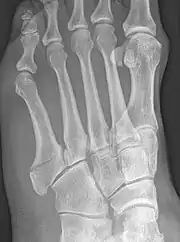

Robert Jones described the fracture of the fifth metatarsal which bears his name in the Annals of Surgery in 1902. In his paper, Jones described the fracture in a series of six patients, the first of which was himself.[8] He had injured his foot while dancing several months earlier, and had thought the injury to be to a tendon in the foot. He examined himself the day after the injury, and found that the tendon was intact, but he could not find definite evidence of bony injury. He asked a colleague, Dr. David Morgan, to X-ray his foot, and a fracture above the base of the fifth metatarsal was found. The finding of similar fractures in several patients after his own prompted him to write about it. He also noted that the fracture was not caused by direct trauma to the bone, as had always been assumed before, but by a cross-strain being applied to the bone.[9]